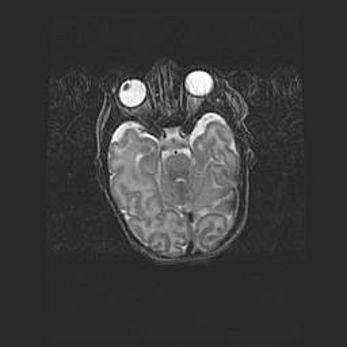

Наружная гидроцефалия с возможной атрофией височных областей.

Возраст: 28 дней

Вес: 3670 г

Пол: мужской

Окружность головы: 38 см

Срок гестации: 40 недель

Гидроцефалия головного мозга у новорожденных – это заболевание, которое характеризуется скоплением избыточного количества спинномозговой жидкости в желудочковой системе головного мозга в результате затруднения её перемещения от места выработки к месту поглощения в кровеносную систему или вследствие нарушения абсорбции. При открытой наружной форме гидроцефалии у новорожденных расширяются и переполняются субарахноидные пространства.

При нормотензивных  формах,  которые,  как  правило,  являются  следствием  перенесенных ишемических  повреждений  паренхимы  мозга,  возможно  сочетание микроцефалии  с нормотензивной гидроцефалией. В основе данных изменений лежит атрофия больших полушарий с преимущественной  локализацией  в  лобно-височных  областях.